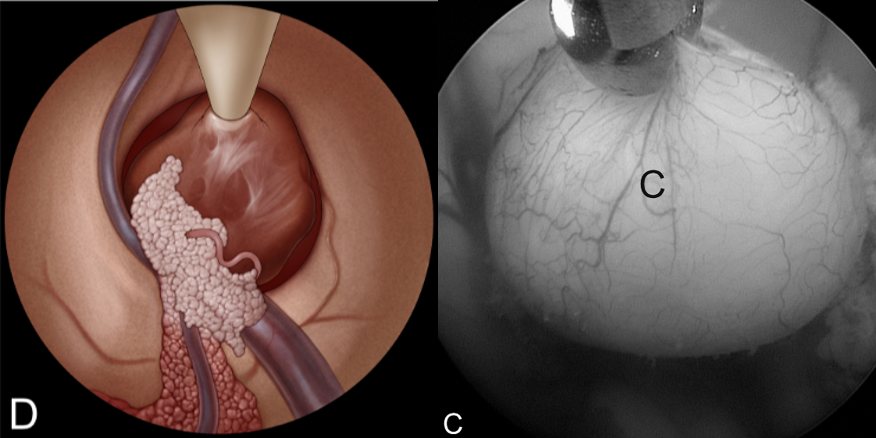

施罗德教授多幅精美插图展示了胶样囊肿切除的手术步骤:

A:检查室间孔,可见胼胝体(F)、脉络丛(CP)、透明隔静脉(SV)和丘纹静脉(T)。室间孔被胶样囊肿(C)阻塞。

B:用双极电凝脉络丛。

C:用剪刀切开囊肿包膜。

D:用吸引管吸出囊肿内容物,像一颗剥壳荔枝。(右侧为真实术中场景)。

E:将囊肿移入侧脑室。

F:采用双手手术技术暴露囊肿蒂。通过左侧通道插入一把可弯曲的抓钳。主要手术器械通过 2.9 毫米的直工作通道引入。

G:用双极电凝器采用双手手术技术凝固囊肿蒂。

H:用剪刀采用双手手术技术切断囊肿蒂。

I:囊肿切除后检查室间孔。